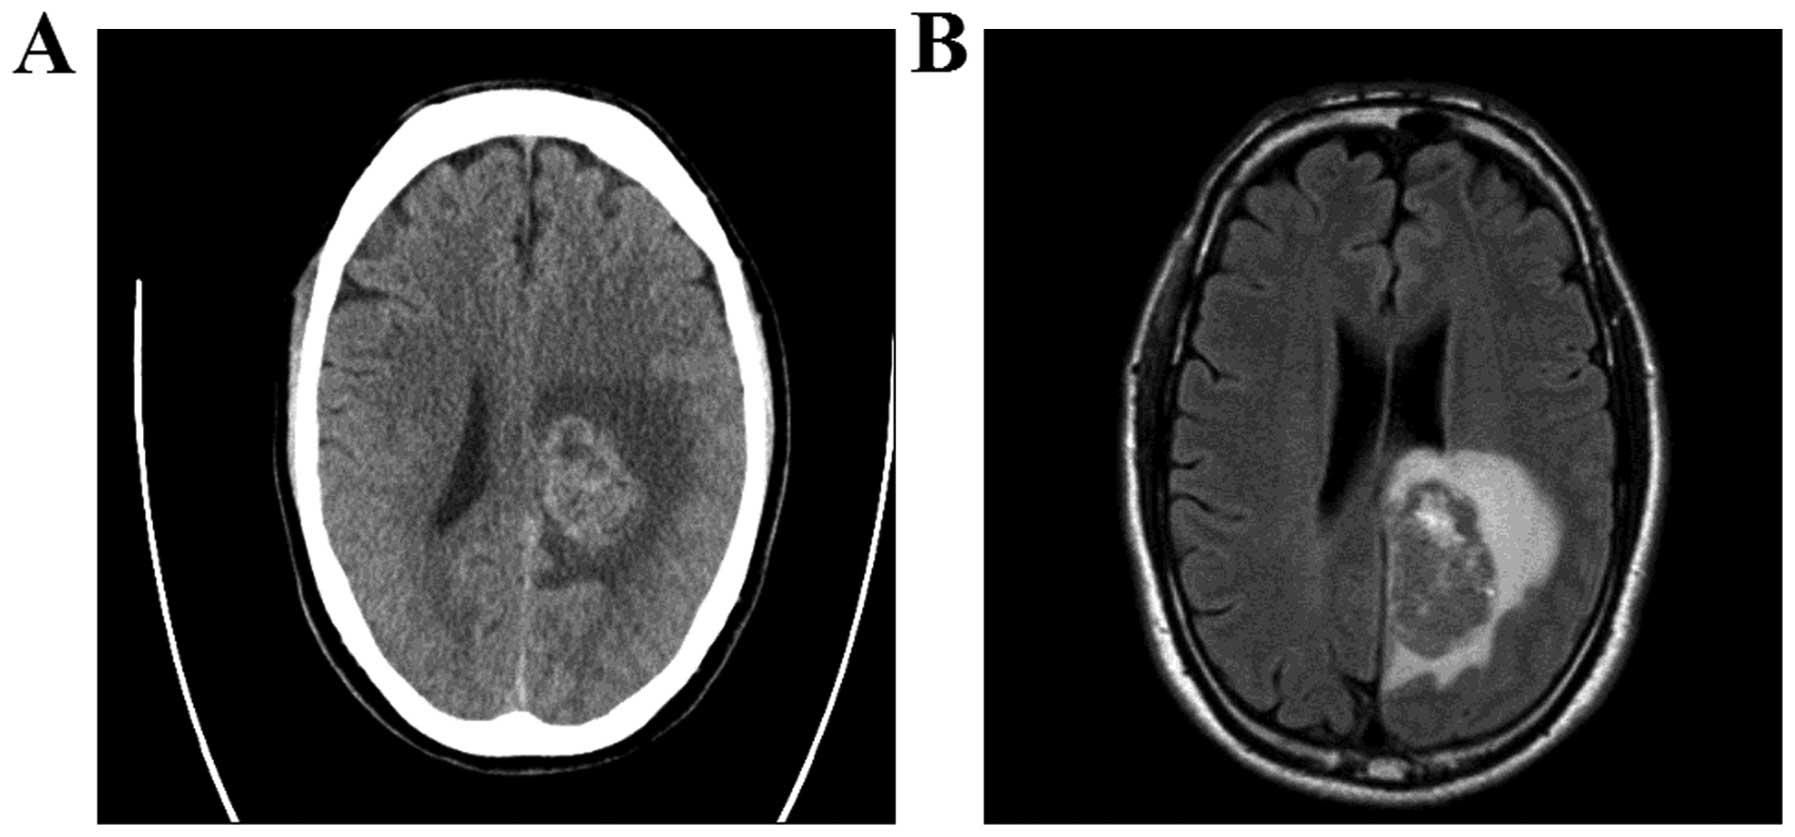

Fazekas grades. Фазекас 2 мрт. Кт мозга. Геморрагическое пропитывание мозга на кт. Токсическое поражение мозга кт.

Fazekas grades. Фазекас 2 мрт. Кт мозга. Геморрагическое пропитывание мозга на кт. Токсическое поражение мозга кт.